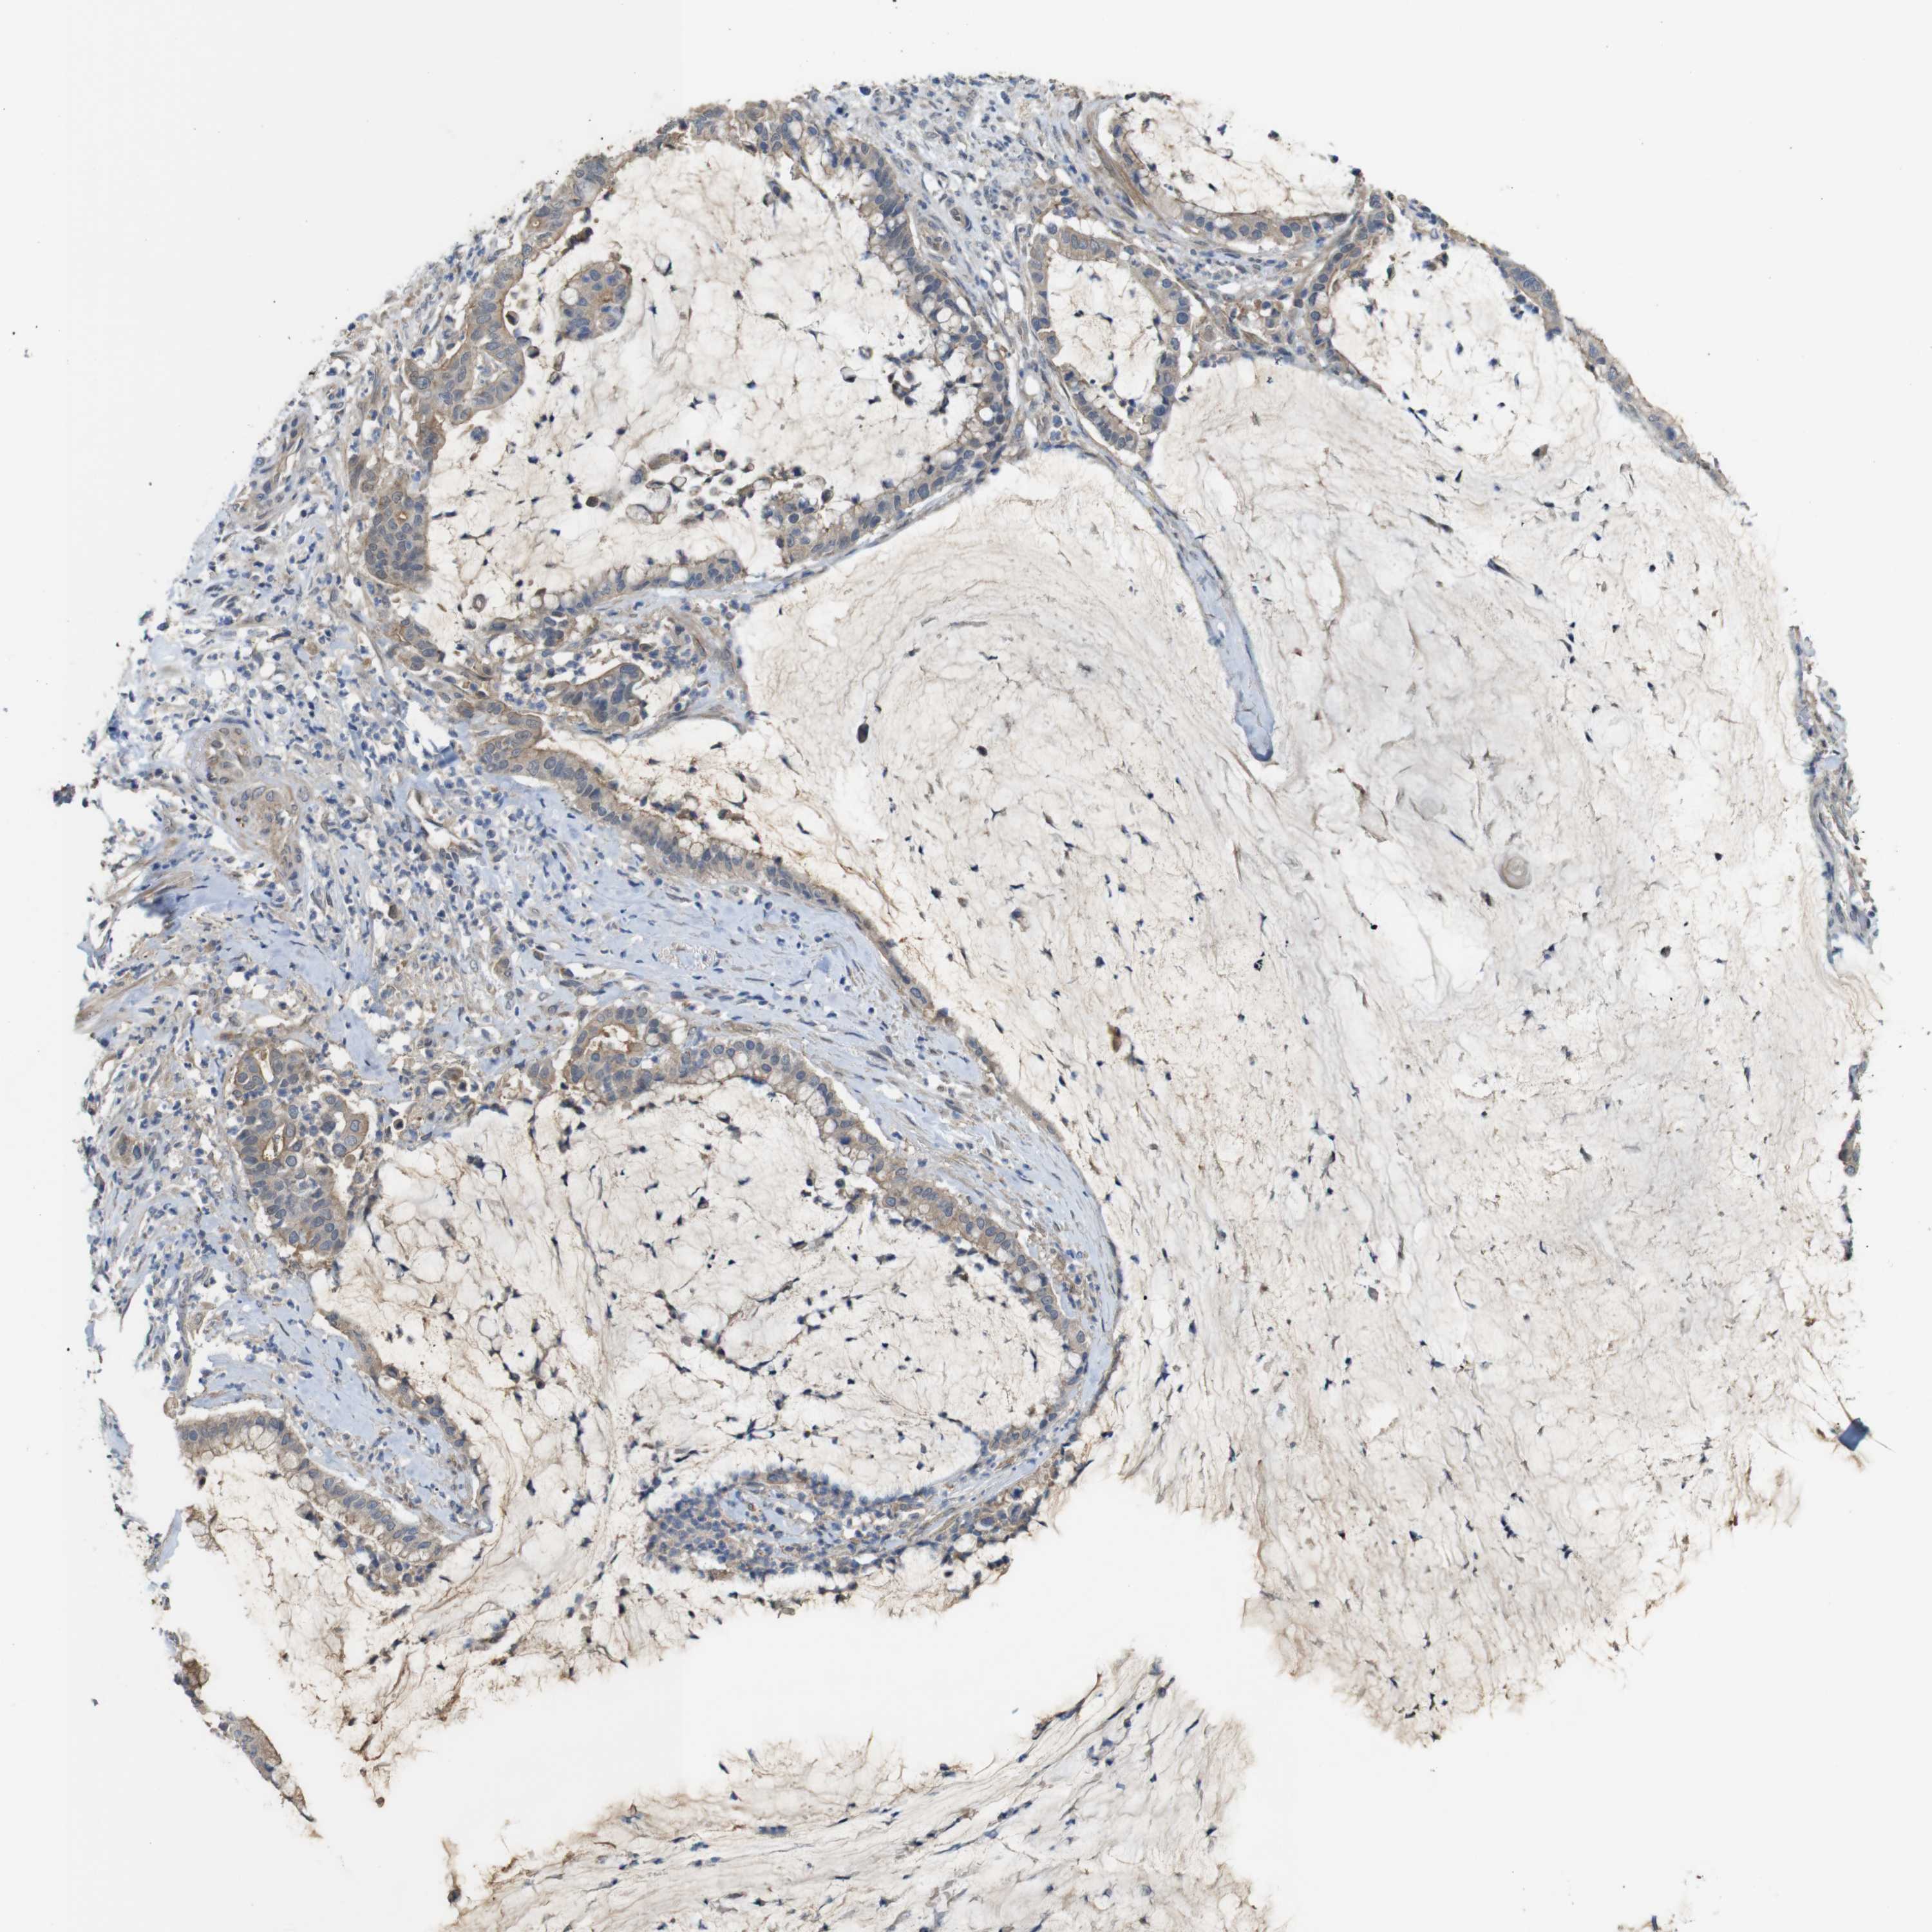

PANCREATIC CANCER - Protein expressioni

A mouse-over function shows sample information and annotation data. Click on an image to view it in a full screen mode. Samples can be filtered based on level of antibody staining by selecting one or several of the following categories: high, medium, low and not detected. The assay and annotation is described here.

Note that samples used for immunohistochemistry by the Human Protein Atlas do not correspond to samples in the TCGA dataset.

Antibody stainingi

Antibody staining in the annotated cell types in the current human tissue is reported as not detected, low, medium, or high, based on conventional immunohistochemistry profiling in selected tissues. This score is based on the combination of the staining intensity and fraction of stained cells.

Each image is clickable and will lead to virtual microscopy that enables deeper exploration of all samples and also displays staining intensity scores, fraction scores and subcellular localization as well as patient and tissue information for each sample.

Antibody HPA002382

Antibody CAB005109

Antibody CAB047311

Staining

High

Medium

Low

Not detected

Intensity

Strong

Moderate

Weak

Negative

Quantity

>75%

75%-25%

<25%

None

Location

Nuclear

Cytoplasmic/membranous

Cytoplasmic/membranous,nuclear

Adenocarcinoma, NOS

Adenocarcinoma, metastatic, NOS